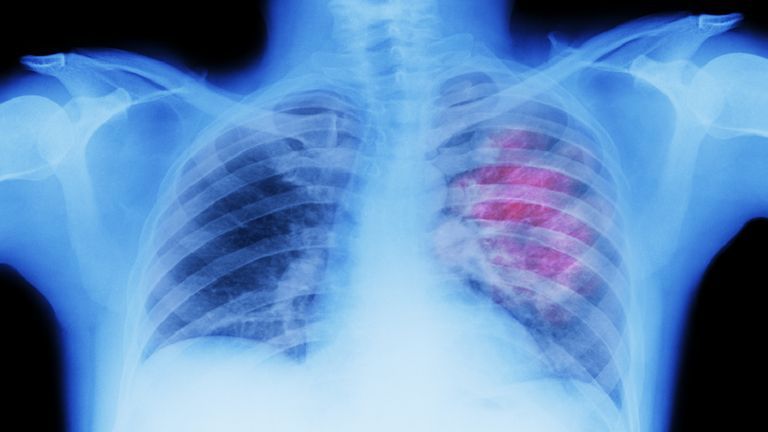

أخبار اليوم – ساره الرفاعي - قالت الدكتورة ماس النسور من قسم طب الطوارئ في مستشفى الجامعة الأردنية إن قسم الطوارئ هو المكان الذي تُقاس فيه الثواني بالذهب، ويتحوّل فيه الهدوء إلى إنعاش في لحظات، مؤكدة أن العمل في هذا القسم «يتطلب ذكاءً وسرعةً واتزانًا عاطفيًا، لأن قرارًا واحدًا قد يُنقذ حياة إنسان».

وأضافت: «في الطوارئ كل شيء يحدث بسرعة. مريض بألم صدر، طفل بحرارة مرتفعة، وحادث سير في اللحظة نفسها. على الطبيب أن يقرر فوراً من يدخل أولاً، من يحتاج إنعاشاً، ومن يمكنه الانتظار. هذا التخصص يحتاج إلى عقلٍ باردٍ، وقلبٍ ثابت، وأيدٍ تتحرك بثقة تحت ضغط لا يُتصور».

وشددت على أن قسم الطوارئ ليس مكاناً للحالات البسيطة أو المزمنة، قائلة: «إذا كان لديك صداع بسيط، أو نزلة برد، أو ألم يمكن معالجته في البيت أو العيادة، فهذا ليس مكانه الطوارئ. لأن مراجعاً واحداً لعارض بسيط قد يأخذ وقتاً ومكاناً من مريض آخر يحتاج إلى إنقاذ فوري.»